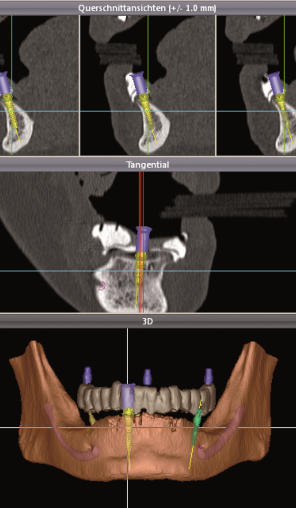

* Implantologie